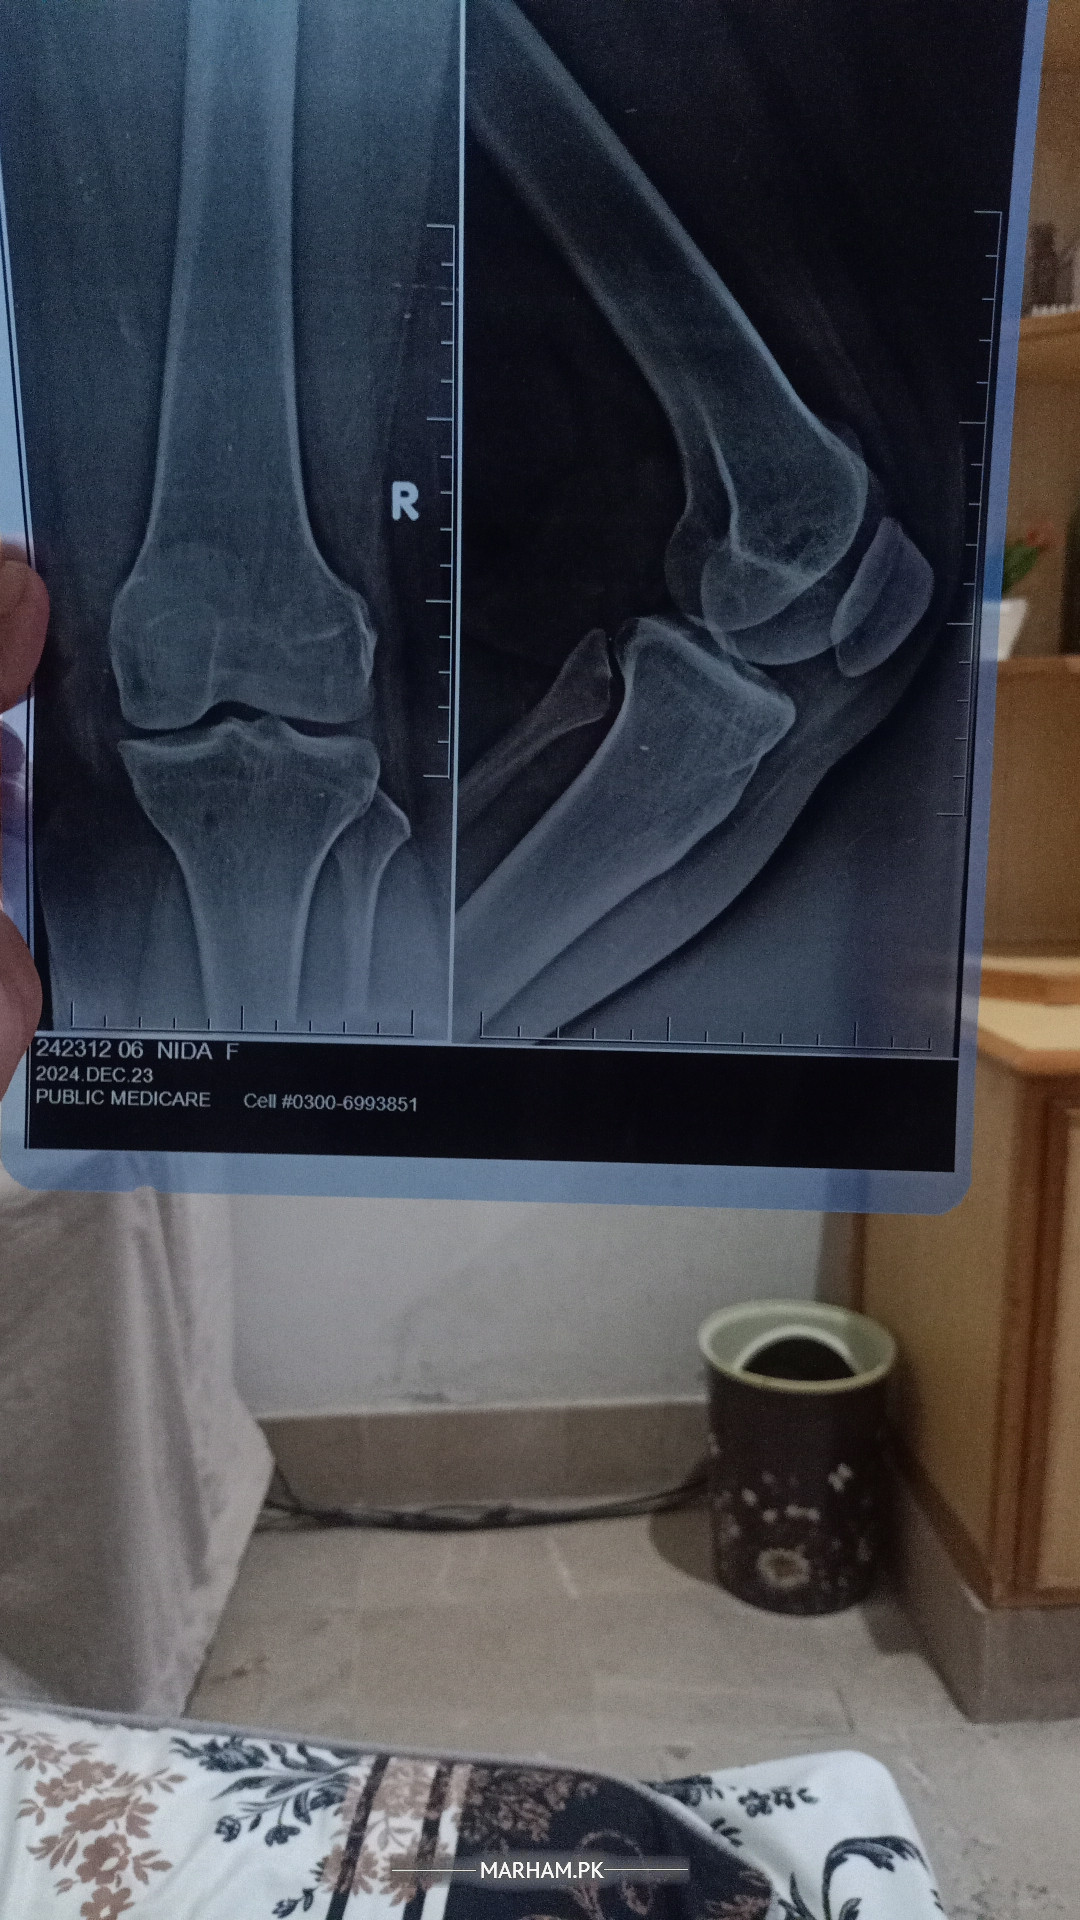

xray b/l knee standing view

Grade 1 osteoarthritis

so,you need to adapt life style modification

and some exercises